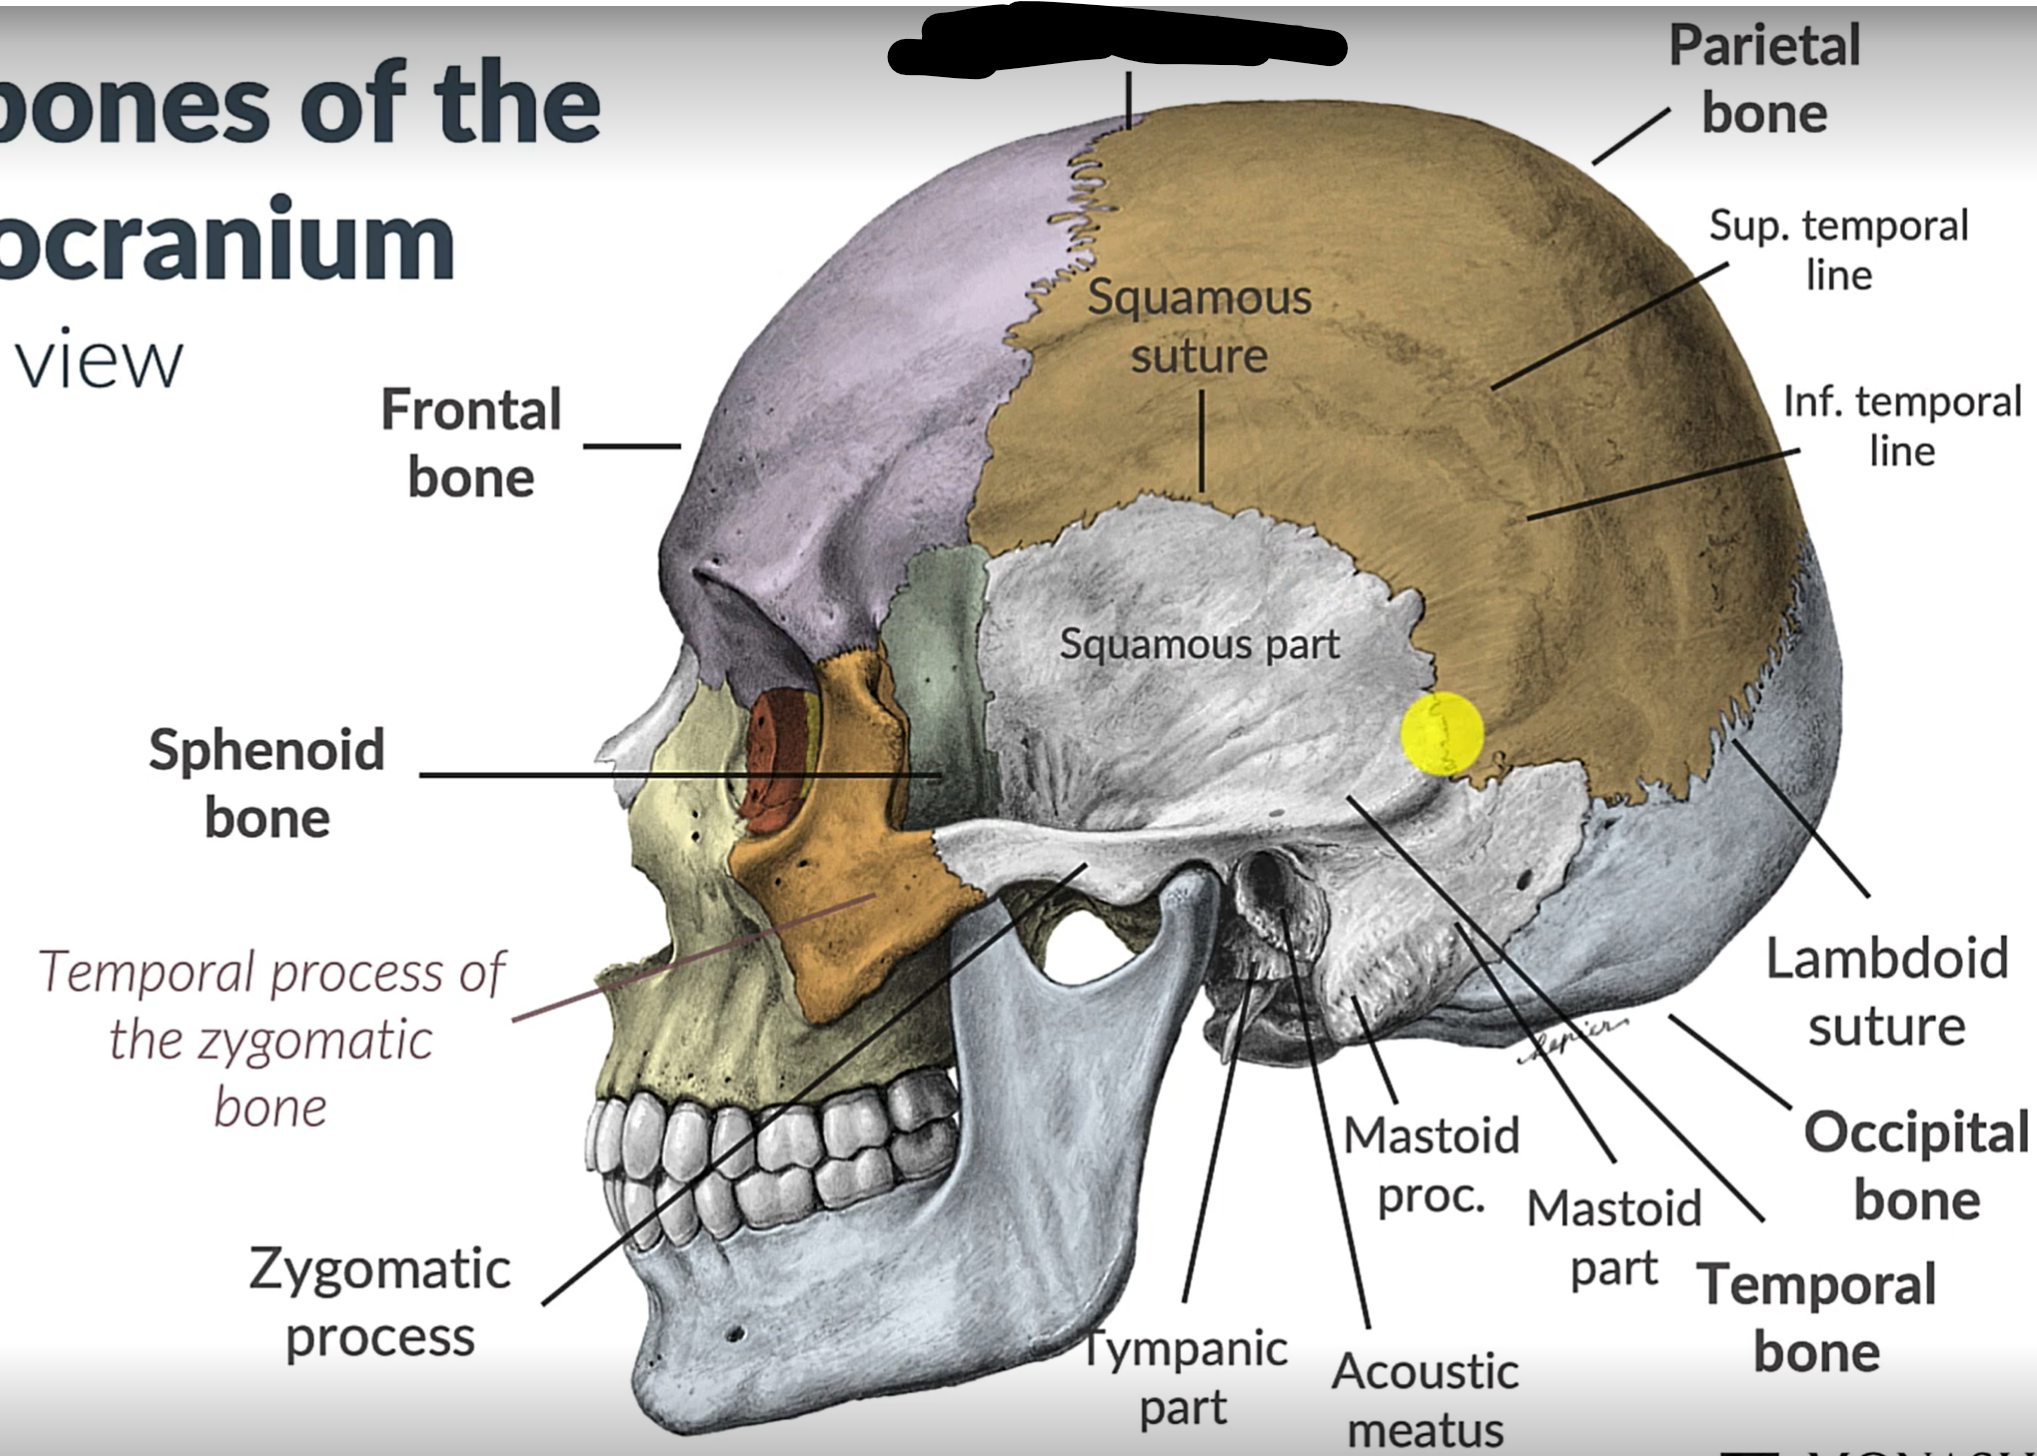

Frontal bone

Coronal suture

Parietal lobe

Squamous suture

Lambdoid suture

Occipital bone

Temporal bone

Zygomatic process

Sphenoid bone

What is the pterion?

The point where the frontal, parietal, sphenoid and temporal bones meet.